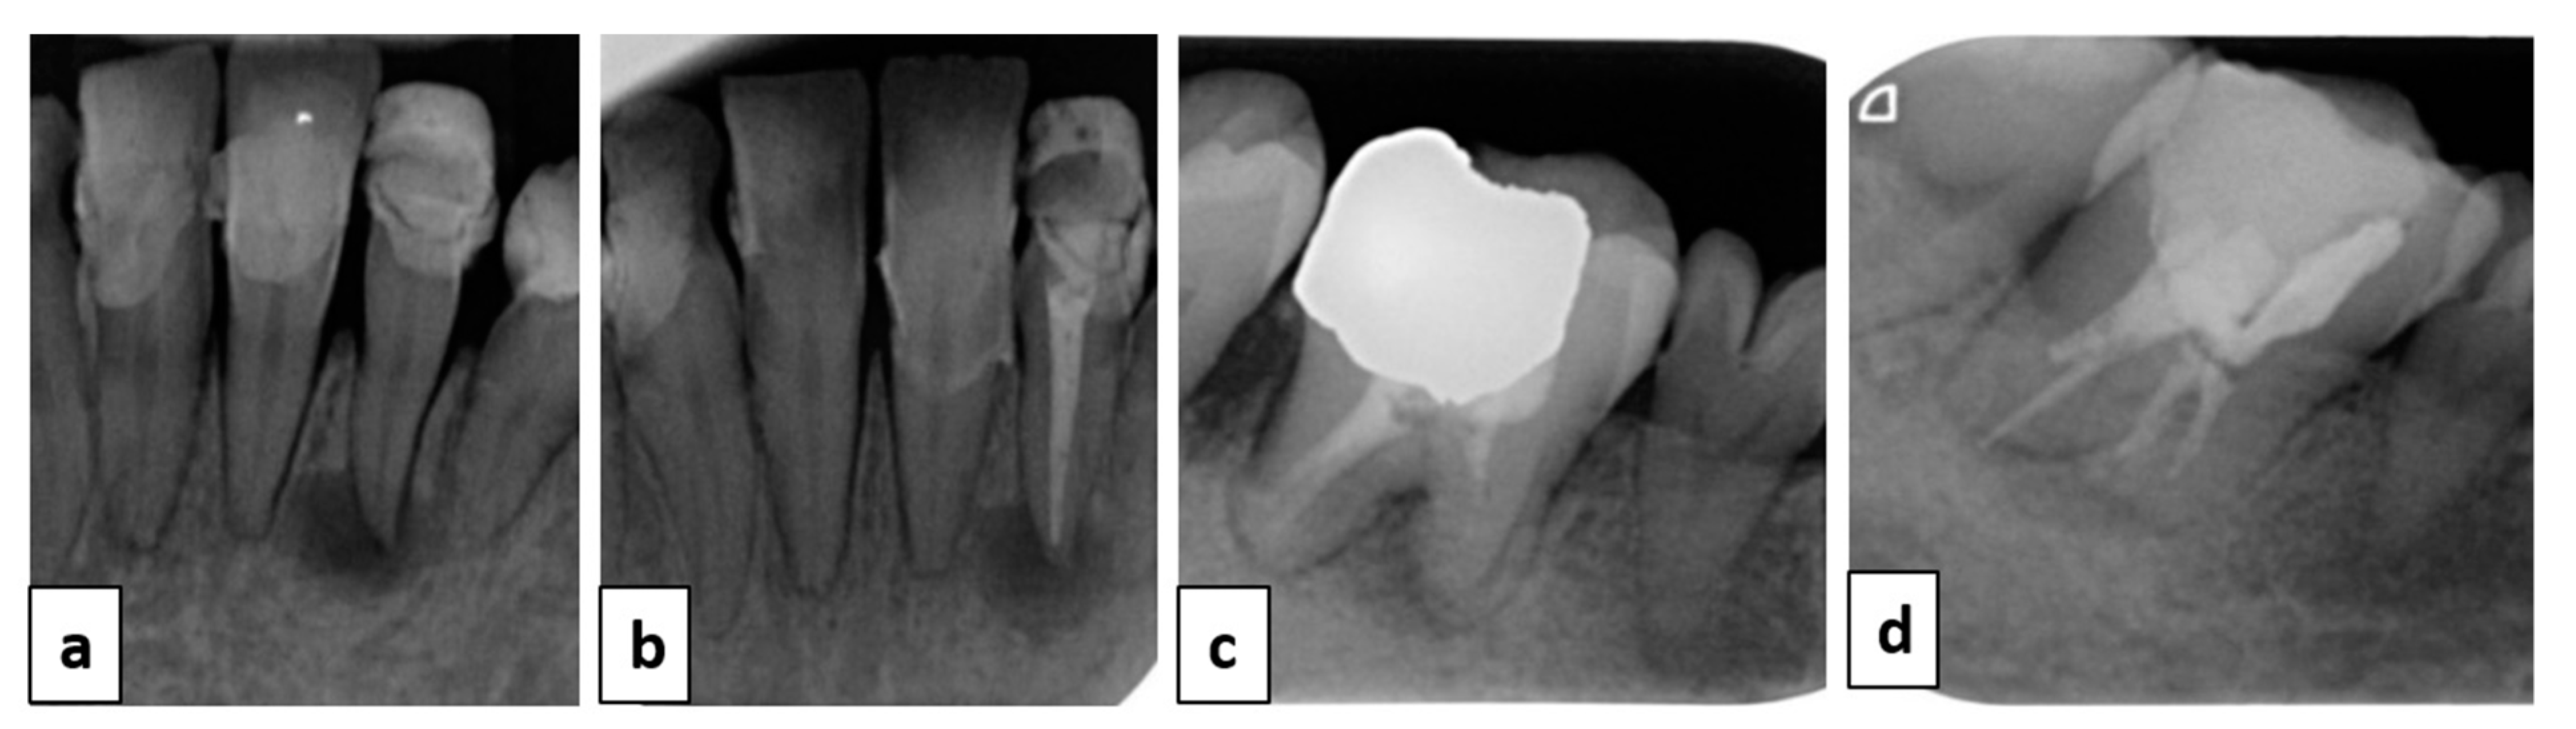

2. Case Report

3. Treatment Plan

4. Therapeutic Management